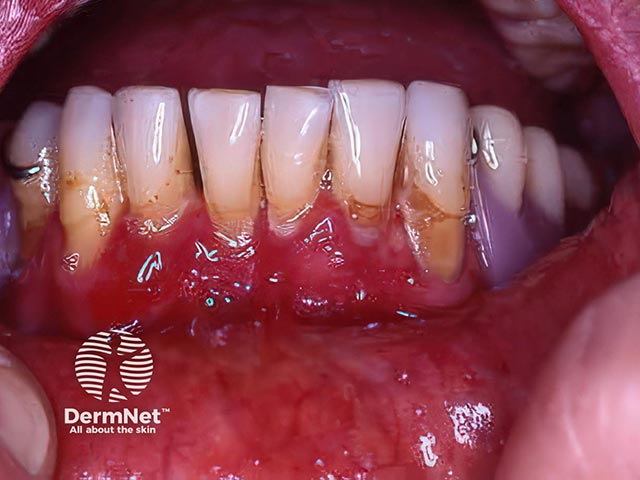

A desquamative gingivitis due to mucous membrane pemphigoid

Desquamative gingivitis due to mucous membrane pemphigoid